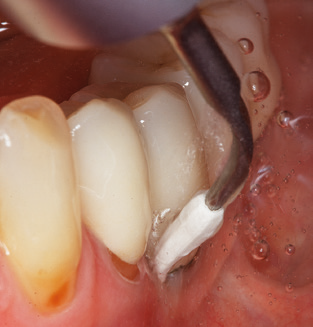

Abb. 4: Für das Sondieren an dentalen Implantaten sind biegsame, millimeterskalierte Sonden empfehlenswert (z.B. Colorvue Kit PCV11KIT6, Hu-Friedy). – Abb. 5a und b: Eine gerade Arbeitsspitze (1P, W&H Dentalwerk Bürmoos GmbH) ist universell für die Instrumentierung natürlicher Zähne geeignet. – Abb. 6: Für die Bearbeitung schwer zugänglicher Bereiche der Zahn- und Wurzeloberflächen (z.B. Furkationen) bieten sich gebogene Arbeitsspitzen (3Pr/3Pl, W&H Dentalwerk Bürmoos GmbH) an. – Abb. 7: Die spitz zulaufende sechseckige Implantatreinigungsspitze (1I, W&H Dentalwerk Bürmoos GmbH) ermöglicht eine atraumatische und effiziente Reinigung der Kronen- und Abutmentoberflächen. – Abb. 8: Für die manuelle Instrumentierung der Implantatoberflächen sind Titan- oder Carbonküretten geeignet.

Die gute Ausleuchtung des Arbeitsfeldes stellt eine wesentliche Erleichterung dar. Bei dem von den Autoren genutzten System ist dies gelungen, indem ein 5­facher LED­Ring in das Handstück integriert wurde. Natürlich werden für dieses System unterschiedliche Arbeitsspitzen für die jeweiligen Indikationsbereiche angeboten. Eine gerade, universell einsetzbare Spitze ist das Basisinstrument zur maschinellen Instrumentierung natürlicher Zähne (Abb. 5a und b). Für schwer zugängliche Bereiche im Seitenzahnbereich werden gebogene Spitzen angeboten, die auch einen Zugang zu freiliegenden Furkationen ermöglichen (Abb. 6).

Unerlässlich für die UPT implantat­ prothetisch versorgter Patienten sind natürlich Arbeitsspitzen für die Reini­gung von Implantatoberflächen. Der Implantatreinigungsaufsatz des hier verwendeten Systems zeichnet sich dabei durch eine spitz zulaufende sechskantige konische Form aus. Dieses Design erlaubt ein leichtes atraumatisches Eindringen in die periimplantäre Tasche und zeigt eine gute Reinigungsleistung (Abb. 7).